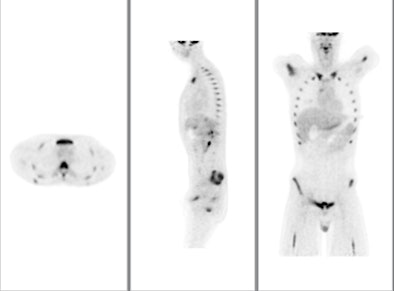

![]() |

| The color PET images are overlaid on a CT scan to show the exact location and extent of disease. The image is from GE Healthcare's Discovery PET/CT 600. Image courtesy of GE and the Cancer Treatment Center of America of Tulsa, OK. |